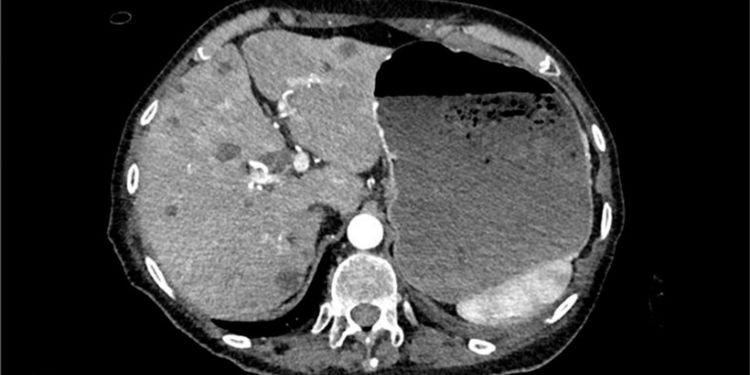

Massive Hematemesis as Initial Presentation of Advanced Pancreatic Adenocarcinoma